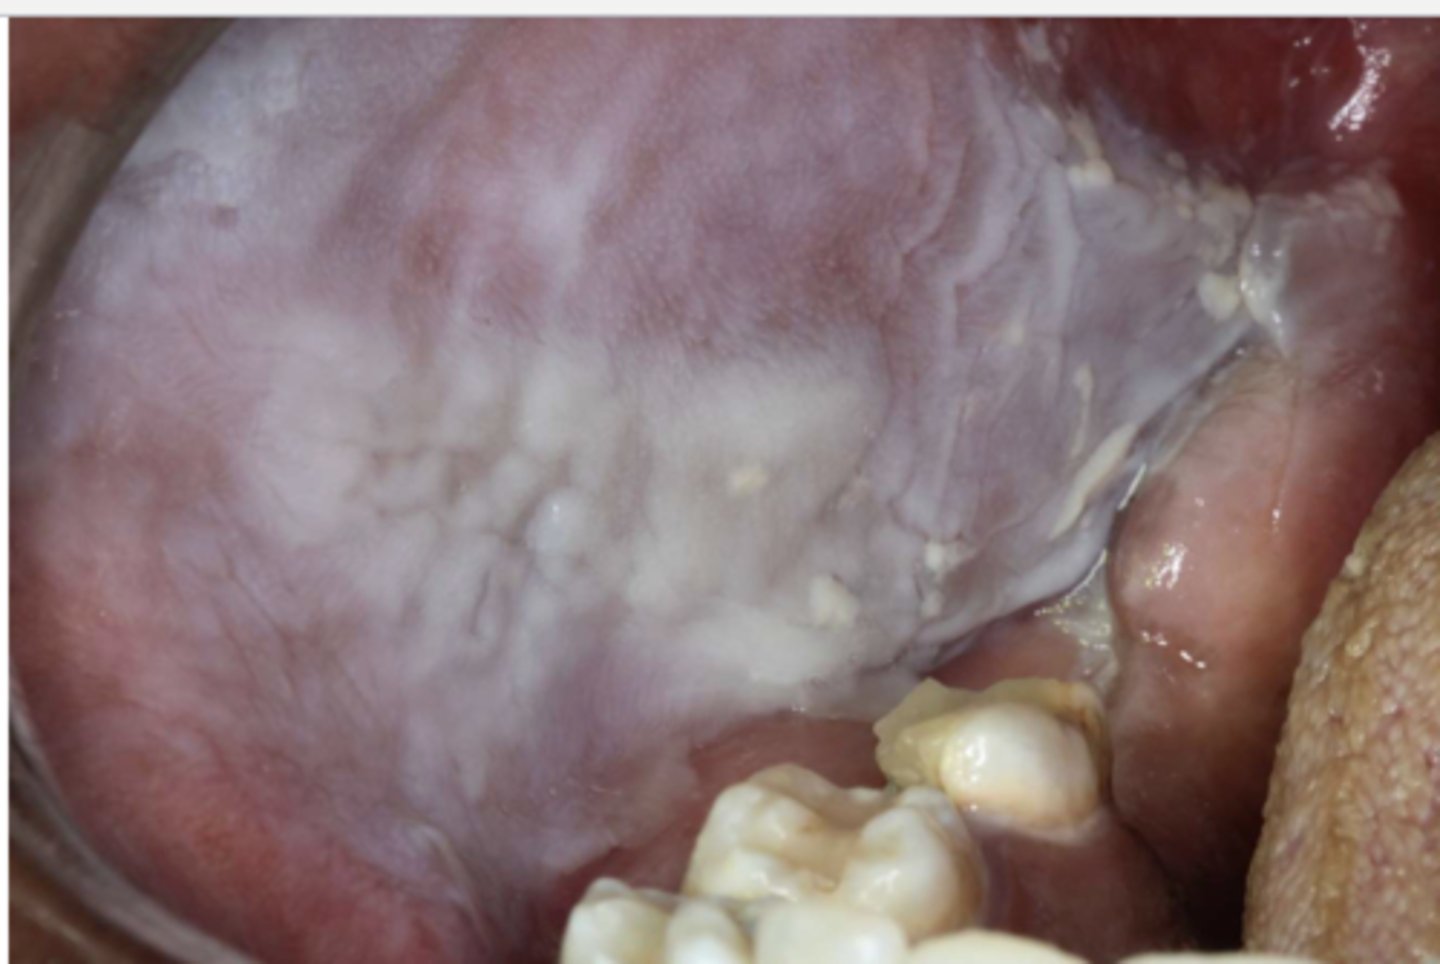

what are these clinical features of?

-hard palate beneath denture base

-pink or pebbly mucosa

-erythema --> suggests secondary candidal infection

inflammatory papillary hyperplasia

what do you suspect?

inflammatory papillary hyperplasia w/ secondary candidal infection

*can tell pt also has candidiasis b/c of erythema